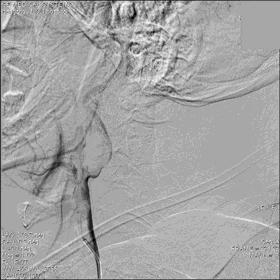

▼21:27穿刺成功,TOT 297min。左侧颈总动脉末端、颈内动脉起始部及颈外动脉起始部长条状血栓形成,随血流晃动,同侧大脑中动脉、大脑前动脉显影良好。